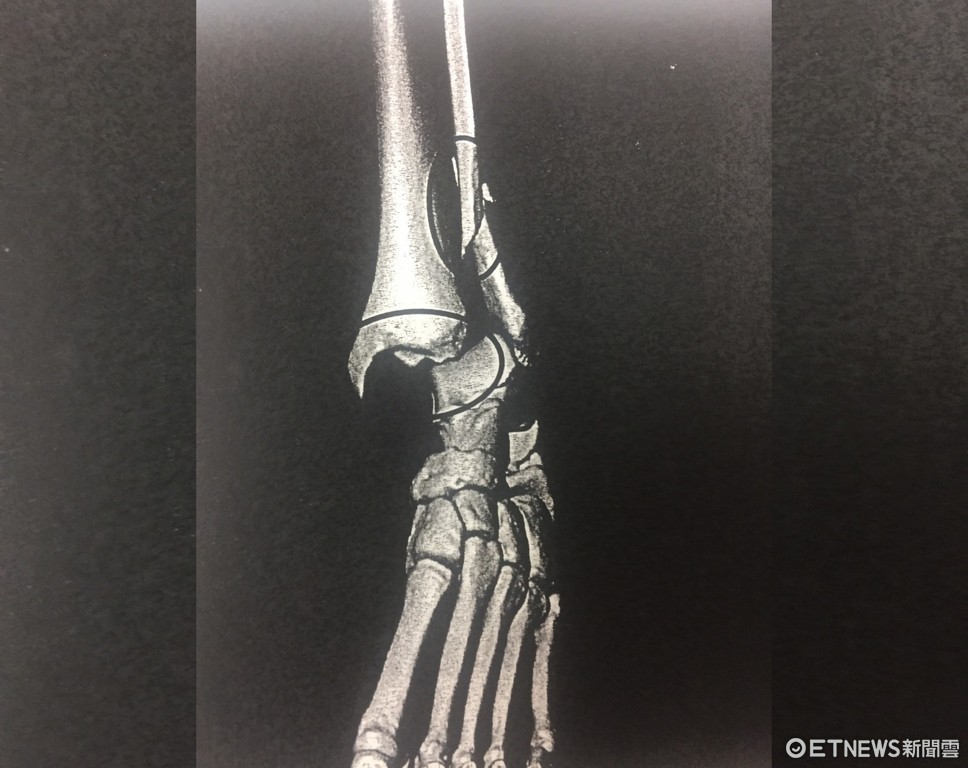

▲林姓男子指稱自己遭斧刃腳偷襲,導致腳骨斷裂。(圖/記者陳豐德翻攝)

警方調查今年二月間36歲的林姓男子在新莊體育館參加武術社團練習,結束後林男隨即找上張男切磋,前兩回合張男皆位居下風,遲遲無法破解招式,就在林男收手之際,張男突然出腳偷襲,造成林男右腳踝受傷倒地,送醫檢查發現左腳腓骨斷裂腳踝脫臼。

社員聽到哀嚎聲上前關心,通報救護車到場將林男送醫;社團教練趕抵現場查看,才驚覺林男是遭到社團的禁忌招式「斧刃腳」所傷,由於此招專門攻擊膝蓋或腳踝關節處,遭擊中者輕則挫傷,重則斷骨,所以平常練習時皆嚴禁使用。